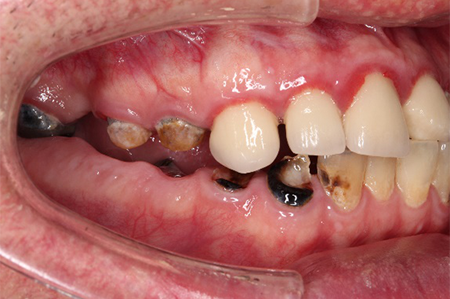

この患者様は長い事歯科医院には通っておらず、下の歯は前歯以外は全て崩壊していることが分かります。

前から見ても歯が欠けてしまい、歯茎も赤く腫れてしまっているのが分かります。

一般的には入れ歯が妥当かと思われますが、患者様は33歳、まだまだ人生は長いです。

奥歯がないと前歯でしか噛めなくなってしまい、残っている前歯もいずれダメになってしまいます。

また、奥歯がなくなってからの期間が長かったため、入れ歯が入るスペースが奥にないのが分かります。

様々なことを鑑み、患者様とも何度も話し合いを行い、下の奥歯には必要最低限のインプラントを、他の歯も外科処置を施しなるべく歯を抜かない方法を取りました。

最終的に抜歯した本数は下の歯5本。上の歯に関しては全て残すことが出来ました。

奥歯があることで前歯の負担を減らし、前歯を失うリスクを下げることが出来ます。